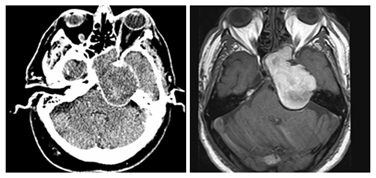

Treatment: An endoscopic approach with sphenoidotomy was performed, showing a pulsatile encapsulated mass (Figure 2). After the aperture of the capsule, samples of the lesion were taken and a big part of the mass was aspirated. During drainage of the mass content the patient suffered fluctuations in his heart rhythm, thus a complete emptying of the mass was not done in order to avoid decompression of the brainstem and the possible risk of cerebral hernia.

Figure 2 Endoscopic sphenoidotomy showing the pulsatile encapsulated mass.